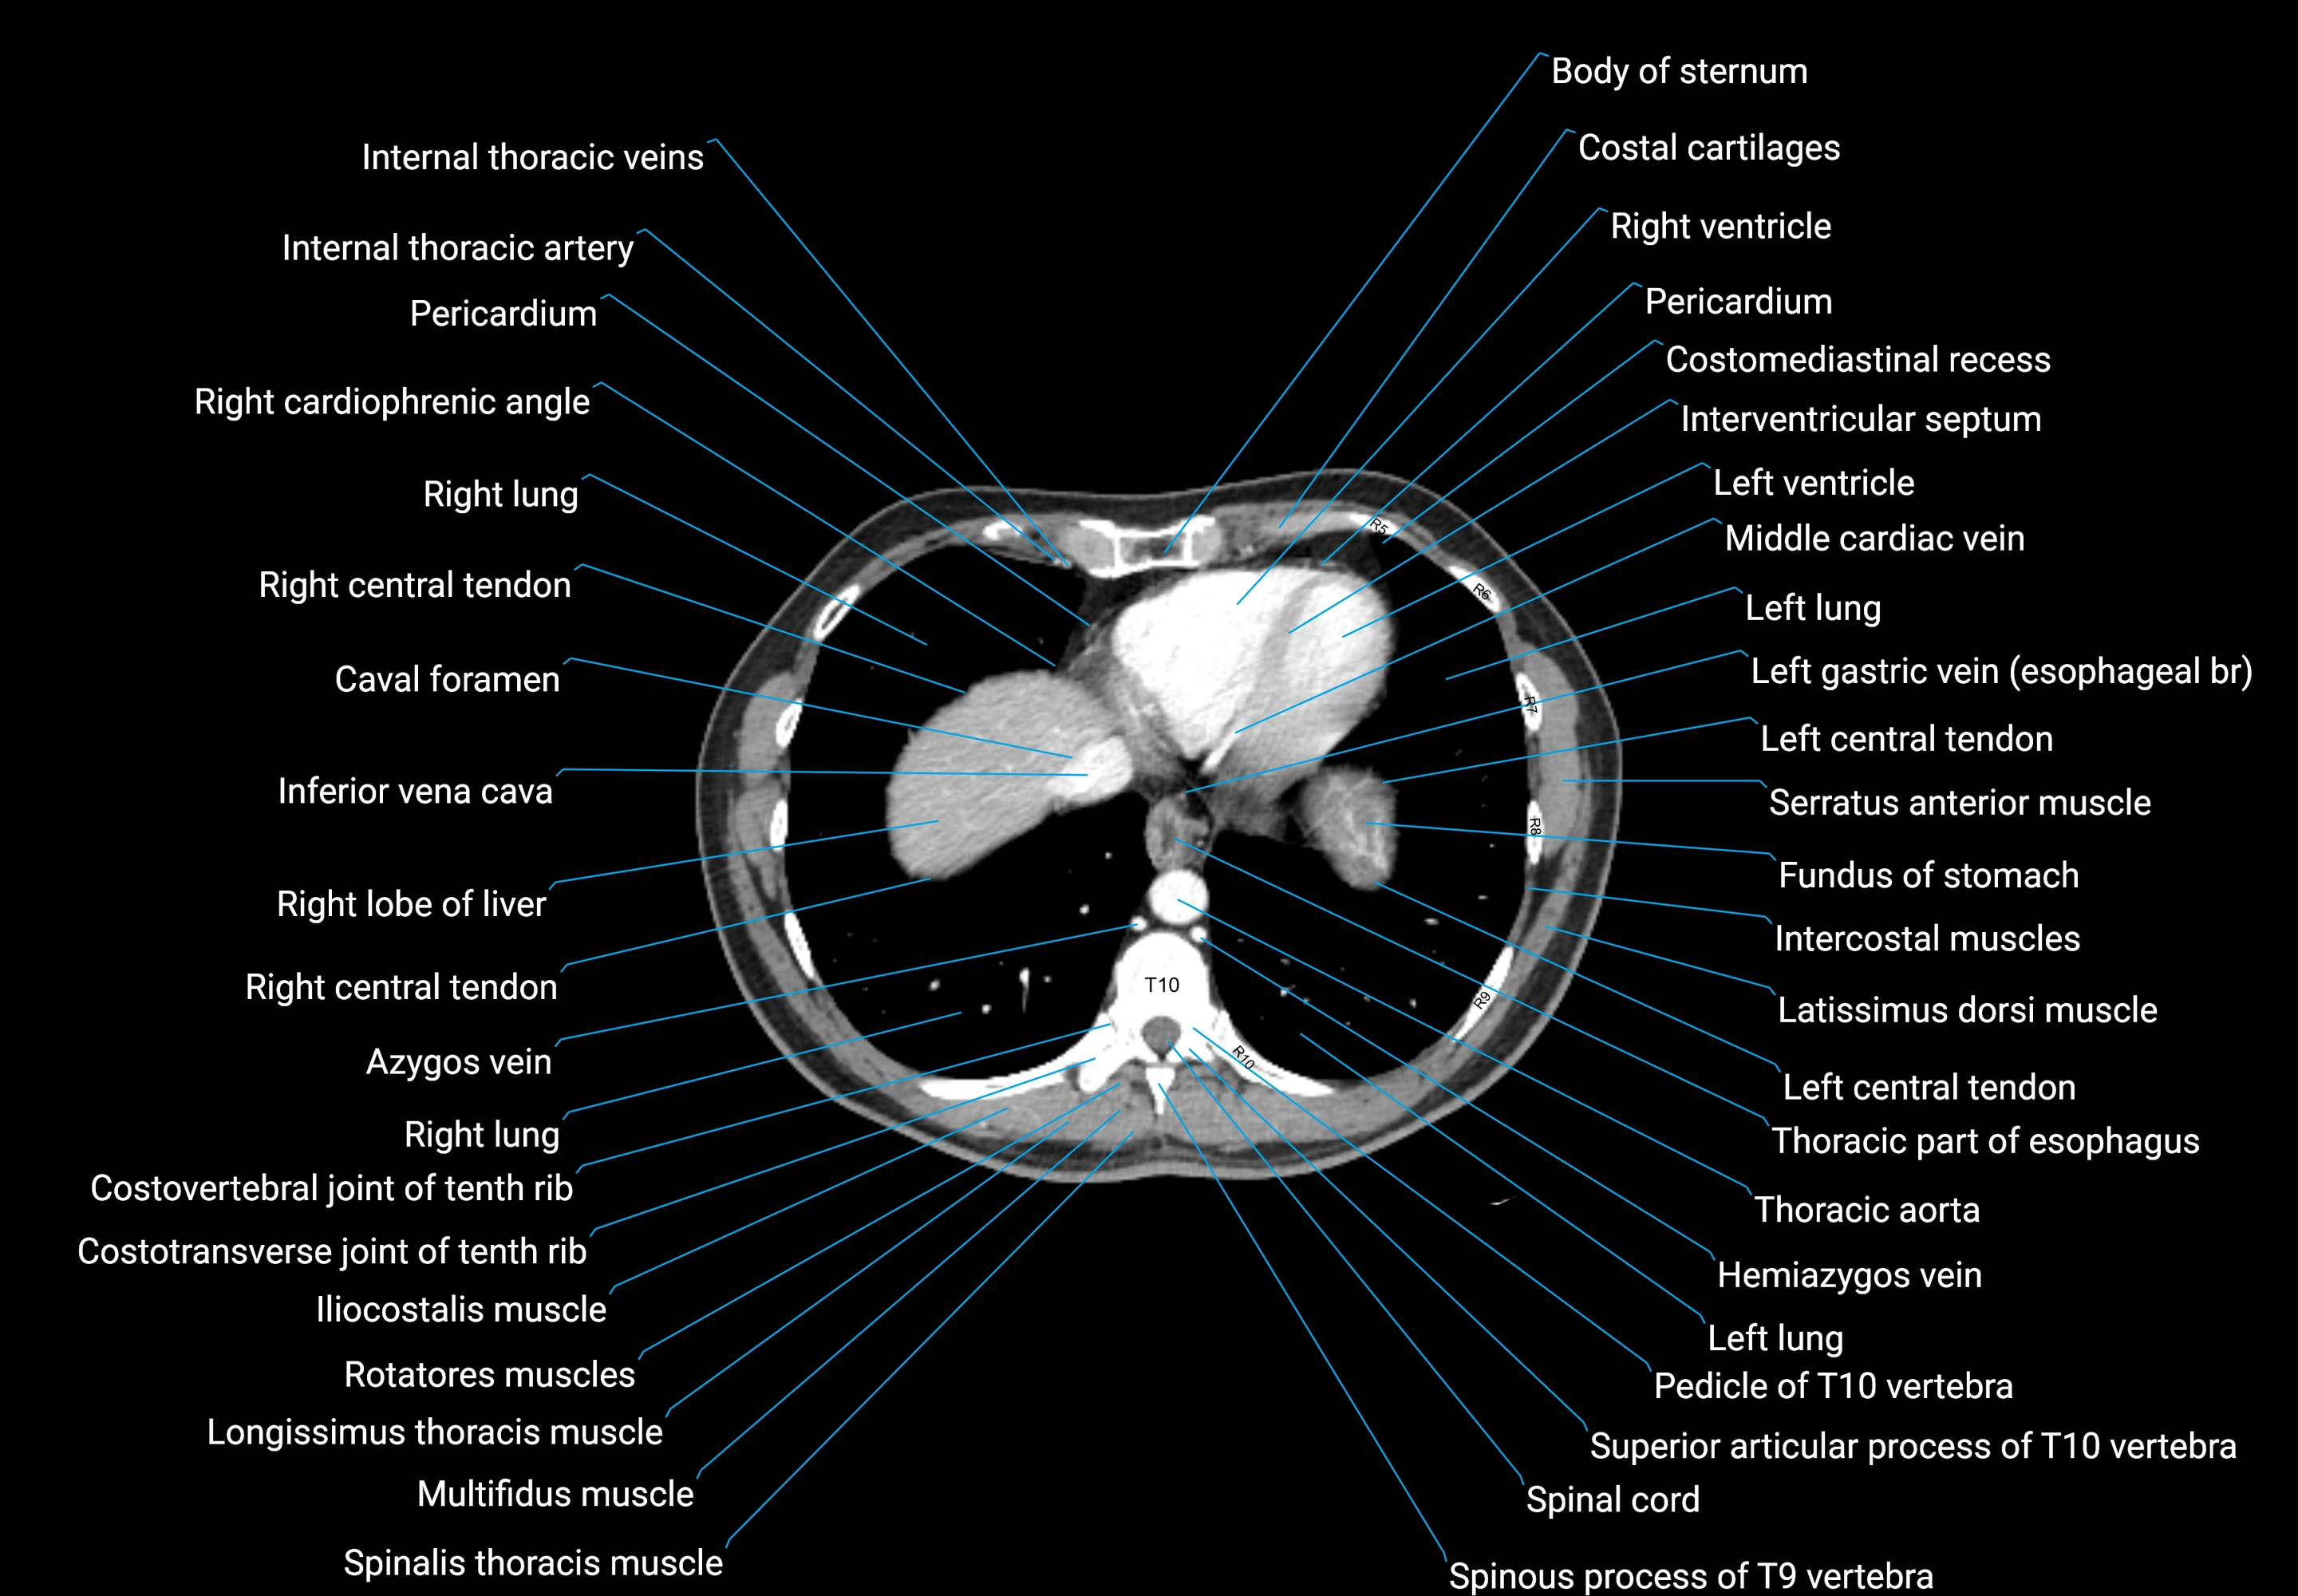

CT images